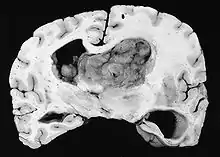

| GFAP stained microscopic section of a subependymal giant cell astrocytoma | |